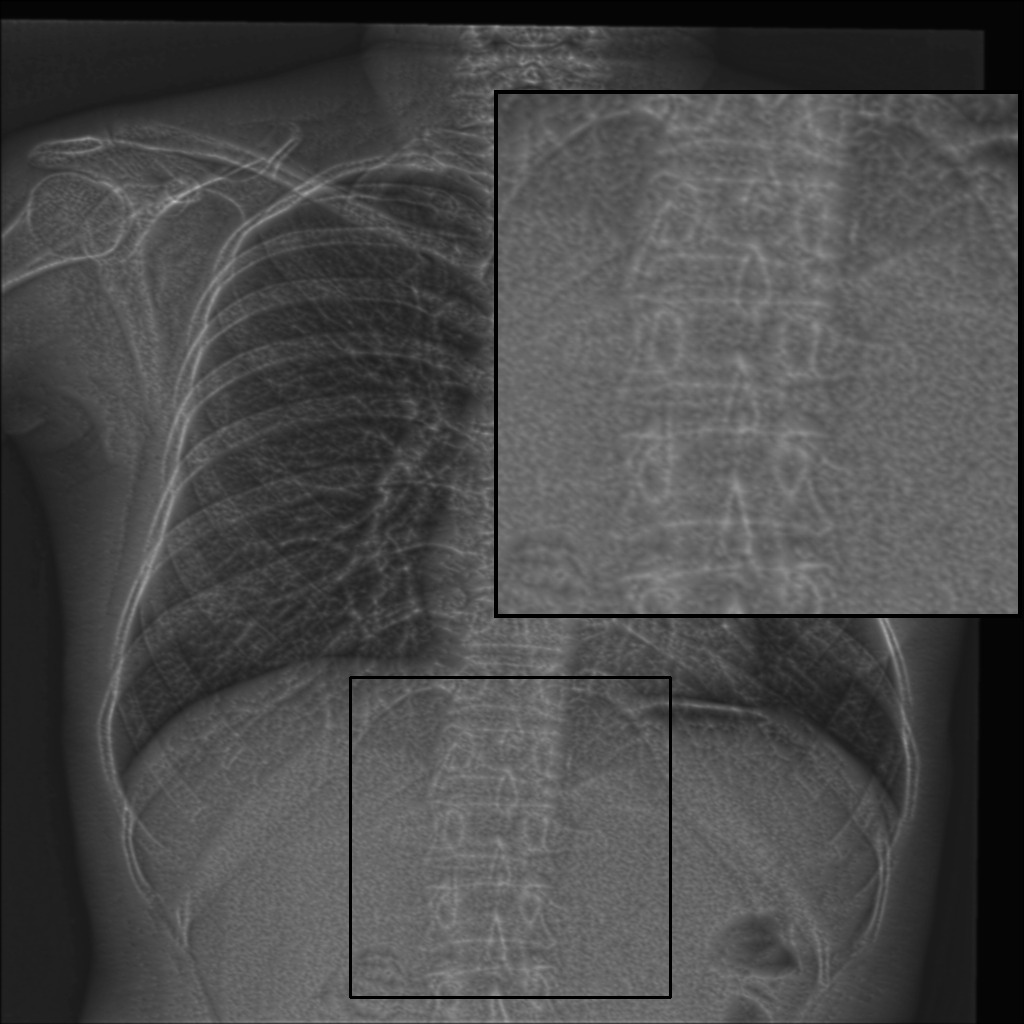

Statistical analysis using the Wilcoxon rank test (applied to scores within the range of mean ±\pm 1.96 standard deviations) confirms the significance of improvements in TC, LPC-SI, TMQI, and PIQE (p<0.05p<0.05). Interestingly, the model without GL exhibits significantly higher entropy (p<0.05p<0.05), although this metric alone does not necessarily indicate superior structural or perceptual quality. Furthermore, gradient map visualizations (see Fig. 5) provide additional insight into the GL’s contribution, revealing clearer object outlines and finer details in comparison to settings without the GL.

Refer to caption

Figure 5: Visualization of gradient maps: (a) Original image fragment, (b) gradient of the original fragment, (c) gradient with single HFC as guidance, (d) gradient without GL, and (e) gradient with GL